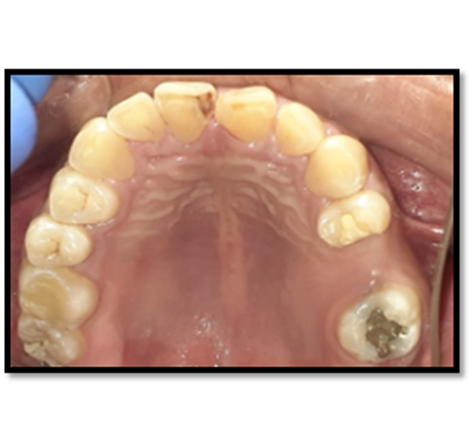

El estudio radiográfico puede evidenciar múltiples sombras radiopacas rodeadas de un halo radiolúcido pertenecientes a un tumor odontogénico CIE10: D164 (odontoma compuesto), localizados en a nivel de los órganos dentarios 4.3; 4.1; 3.1; 3.2; 3.3. También se puede constatar la presencia de una sombra radiopaca que concuerdan con el órgano dentario retenido.

Imagen 2. Radiografica Panorámica.

El órgano dentario retenido tiene una dirección mesioangular, sobrepasando la corona la mitad de la línea media. En íntima relación se encuentra las raíces de los órganos dentarios 4.1; 3.1; 3.2 con los dentículos y adicionándose con la relación del órgano dentario retenido esta la raíz del órgano dentario.

Imagen 3. Radiograficas Peiapical.

Los resultados de los exámenes radiográficos evidencian que se trata un odontoma compuesto que se confirmara con el estudio histopatológico posquirúrgico.

En su gran mayoría en la presentación de este caso clínico se puede observar la presencia de una sombra radiopaca que concuerdan con el órgano dentario retenido 4.2.con una imagen mixta con múltiples radiopacidades muy similares a los órganos dentarios que están rodeados de un halo radiolúcido perimetral que son similares descripciones de investigaciones de otros autores.